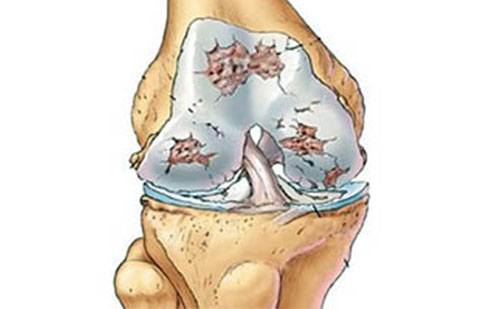

Na artrose ocorre desgaste da cartilagem ao longo do tempo. Com a progressão da doença ocorre exposição da superfície do osso causando dor.

Os principais sintomas da artrose são dor e sensação de rigidez na articulação (joelho).

O tratamento da artrose pode ser realizado de diversas formas de acordo com sua gravidade.

De uma maneira geral, os casos mais leves adequam-se ao tratamento não-cirúrgico e os casos mais graves podem necessitar de cirurgias.